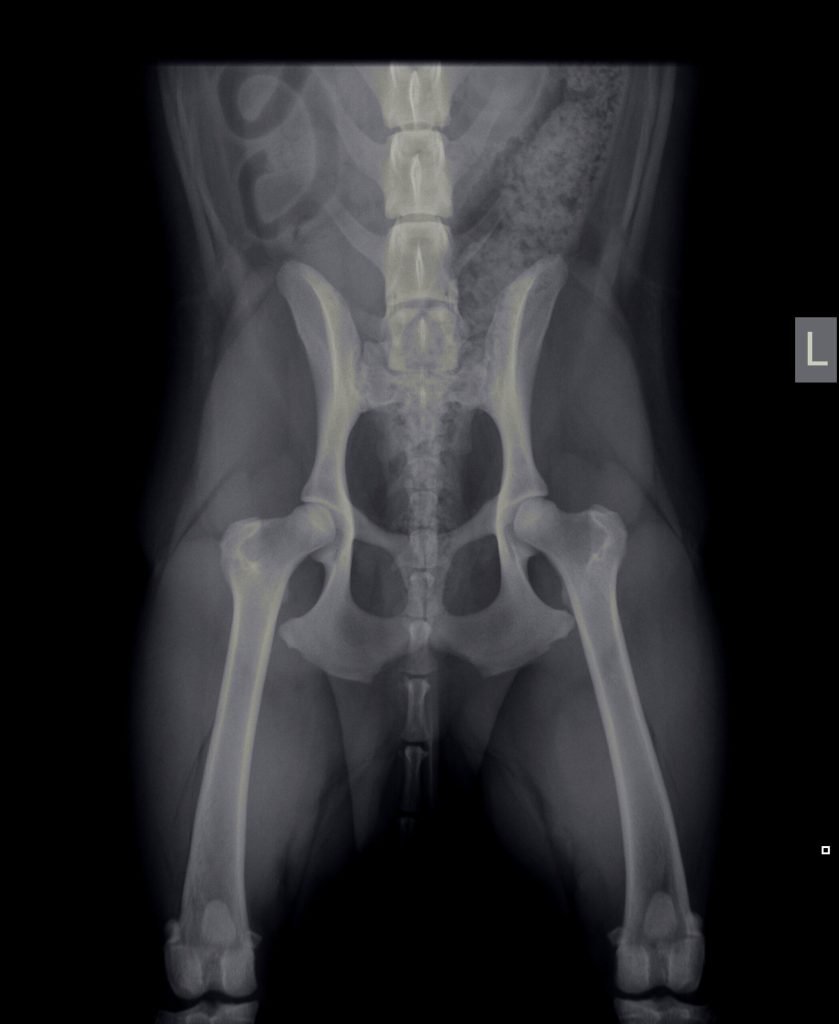

Diagnostiek

Het stellen van een diagnose kan soms net spoorzoeken zijn. Soms is het eenvoudig en soms is het lastig.

Onze diagnostische mogelijkheden hebben we uitgebreid door de aanschaf van vele soorten van apparatuur en het volgen van allerlei cursussen.